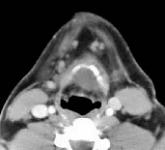

Fig.1 Fig.2 Fig.3 Fig.4

CLINICAL PRESENTATION: This patient presented with a mid-line and left paramidline mobile neck mass and was referred to AIC for a helical CT scan of the neck soft tissues.

HELICAL CT FINDINGS: The CT scan was performed on AIC’s Multi-slice, Multi-detector Helical CT Scanner with 2.7 mm axial sections at 2.5 mm intervals before and during infusion of low-osmolar, non-ionic contrast using a power injector. It shows a lobulated cystic mass (arrows) in the neck at and below the hyoid bone in the midline and to the left of it, with portions of it behind the hyoid bone and portions embedded in the left strap muscle.